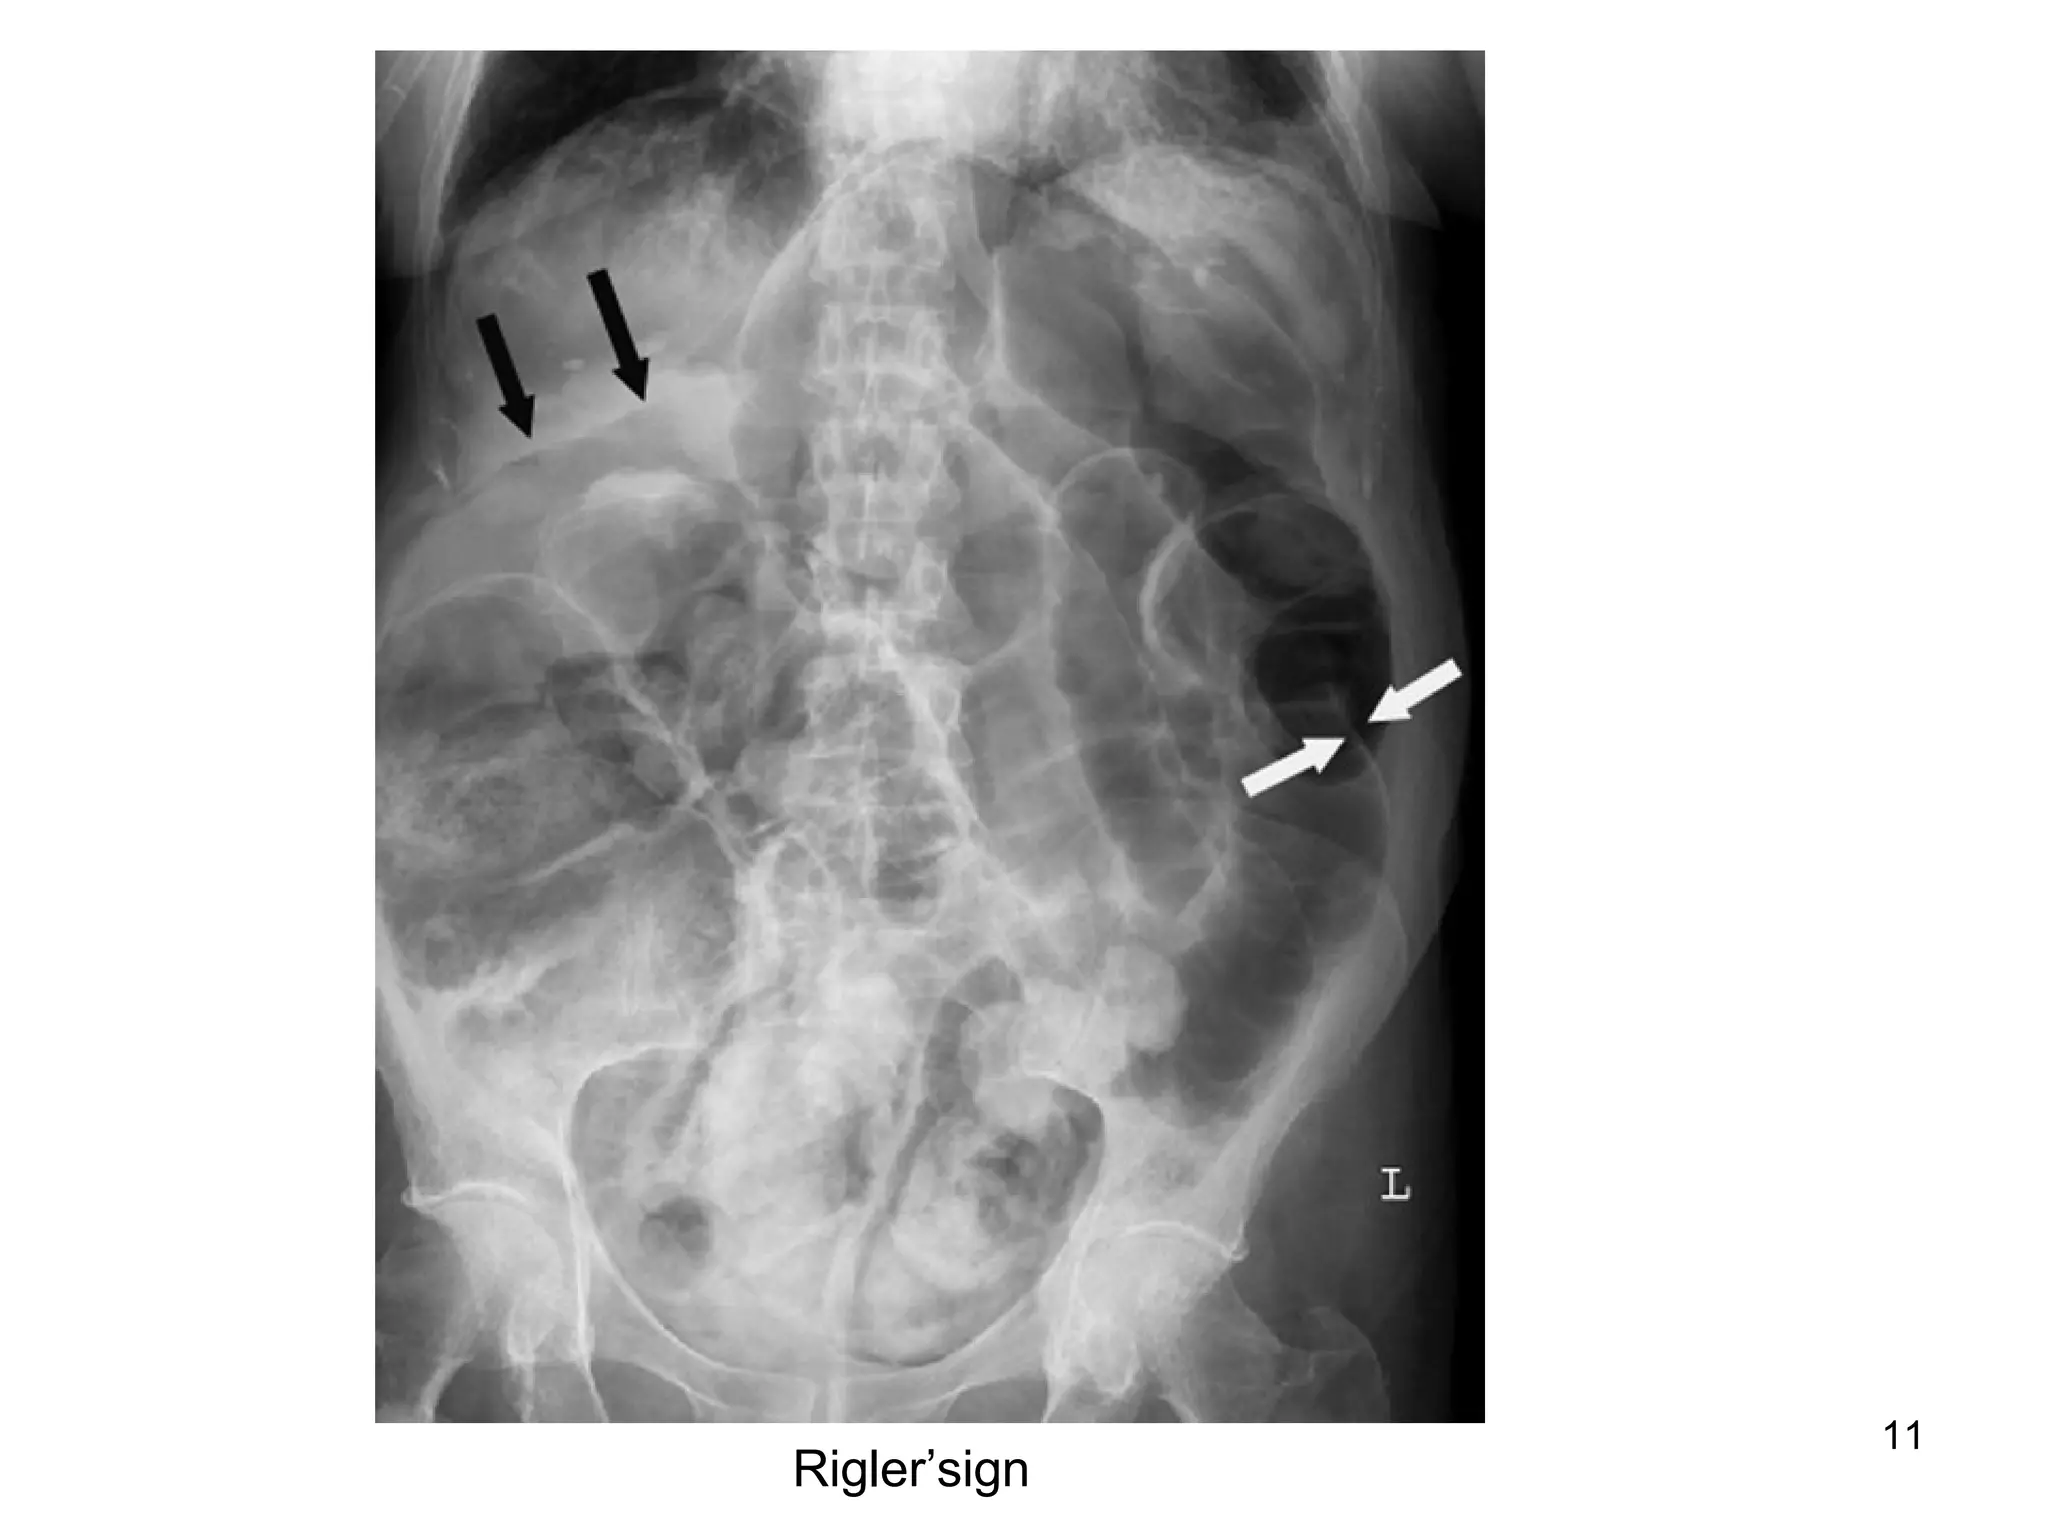

Rigler’sign

10 FPA Centrally placed smallbowel loop Valvulae conniventes